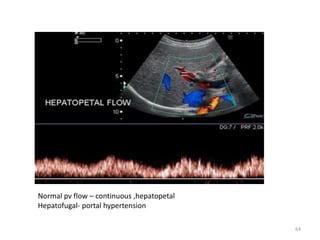

Normal pv flow – continuous ,hepatopetal

Hepatofugal- portal hypertension

Normal pv flow– continuous ,hepatopetal Hepatofugal- portal hypertension 64